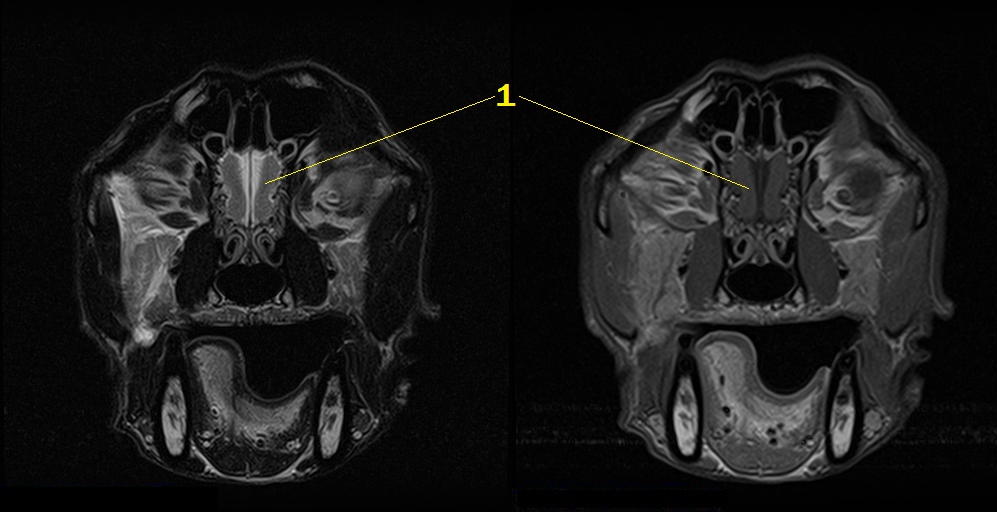

Q. Identify the structures labeled below:

1. Olfactory bulb